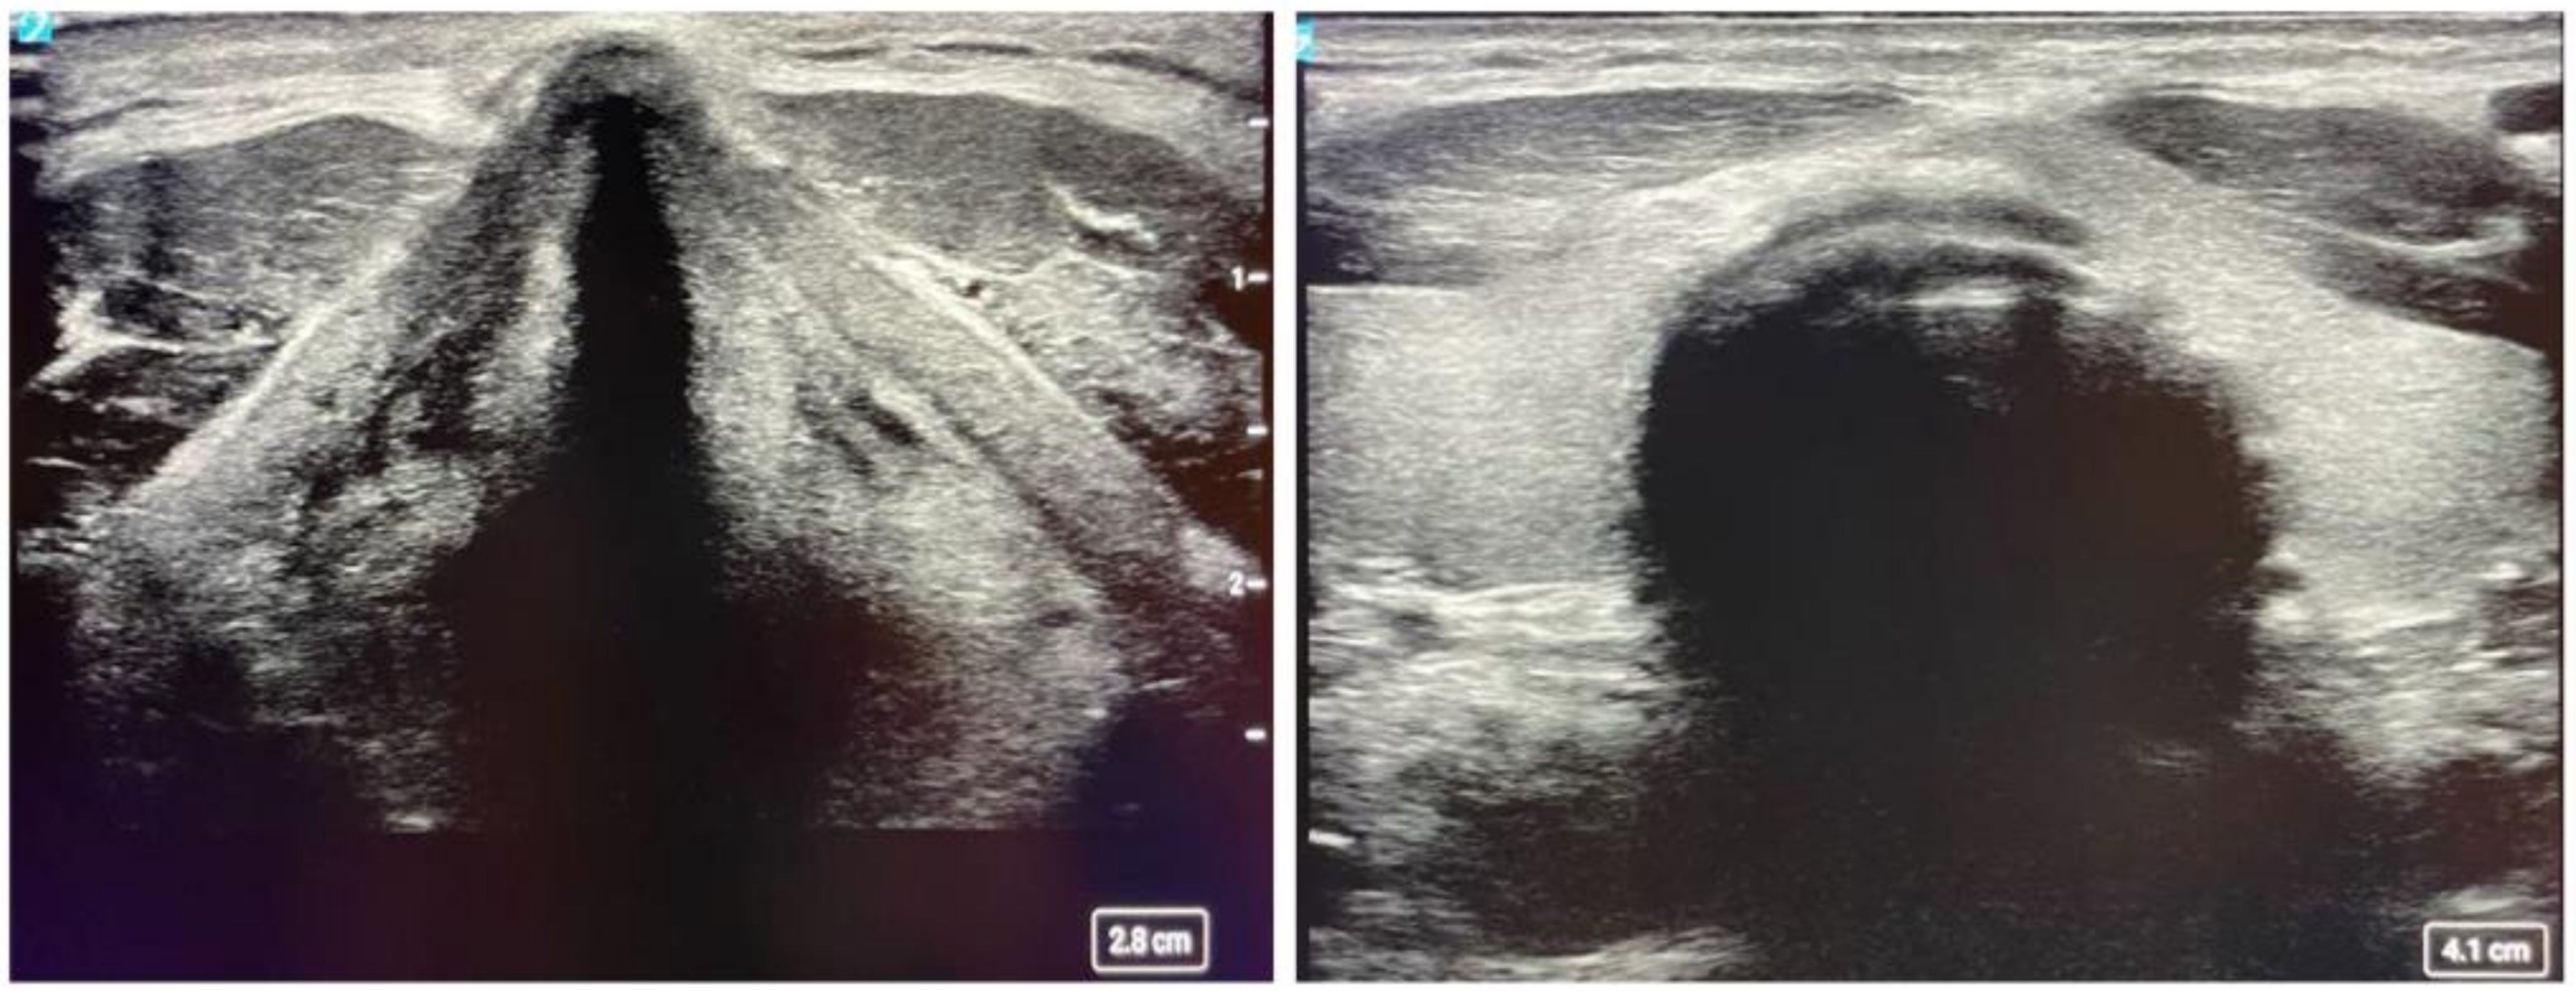

2.2. Neck Ultrasound